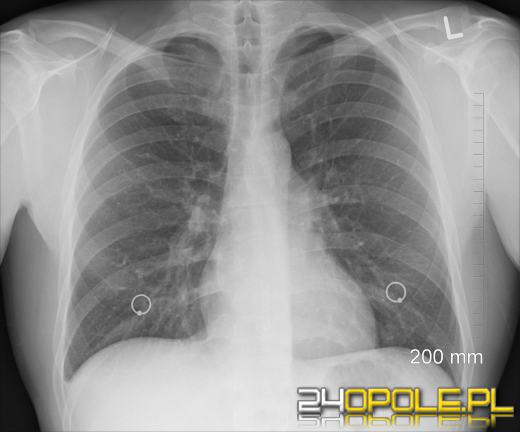

Naukowcy z Wydziału Matematyki i Nauk Informacyjnych Politechniki Warszawskiej pracują nad systemem, który usprawni diagnozowanie i monitorowanie zmian chorobowych w obrębie klatki piersiowej.

Projekt o tej nazwie wesprze lekarzy pulmonologów i radiologów w analizowaniu badań tomografii komputerowej. Sztuczna inteligencja nie tylko wykryje, ale i dokładnie opisze zmiany chorobowe. Zespół MI2.AI kierowany przez prof. Przemysława Biecka, pracuje nad wykorzystaniem możliwości sztucznej inteligencji w procesie interpretacji wyników badań, który bywa wyzwaniem nawet dla najbardziej doświadczonych specjalistów.

- Trenowanie modeli AI to gigantyczne wyzwanie, nie tylko organizacyjne, ale też inżynierskie. Dane mają olbrzymią objętość - w postaci spakowanej 40 TB. Do wytrenowania modelu potrzebna jest olbrzymia moc obliczeniowa - dotąd wykorzystaliśmy ponad 180 tysięcy godzin prac zaawansowanych procesów obliczeniowych typu karty A100, pojedyncze badanie to trójwymiarowa macierz o wymiarach 500x500x300 pikseli. Skala naszego przedsięwzięcia jest unikalna, opracowywany zbiór danych PLIST będzie największą publicznie dostępną bazą danych badań CT klatki piersiowej na świecie. Pierwsza wersja modeli została już opracowana i przetestowana, obecnie szukamy kolejnych partnerów medycznych do współpracy nad testowaniem, wdrażaniem i dalszym rozwojem systemu - mówi prof. Przemysław Biecek, kierownik projektu badawczego.

W pracach nad finansowanym przez Narodowe Centrum Badań i Rozwoju projektem o nazwie "Godna zaufania sztuczna inteligencja wspierająca identyfikację zmian chorobowych w płucach na bazie danych obrazowych" uczestniczy multidyscyplinarny zespół czołowych ekspertów: znawców inżynierii oprogramowania, sztucznej inteligencji, wyjaśnialnego uczenia maszynowego, wizualizacji danych czy radiologii. Badania prowadzone są we współpracy z Polską Grupą Raka Płuca oraz Dziecięcym Szpitalem Klinicznym w Warszawie.

Projekt uzyskał pozytywną oceną merytoryczną przeprowadzoną przez Komitet Sterujący NCBR. Do końca czerwca 2025 roku potrwa wdrażanie projektu badawczego.